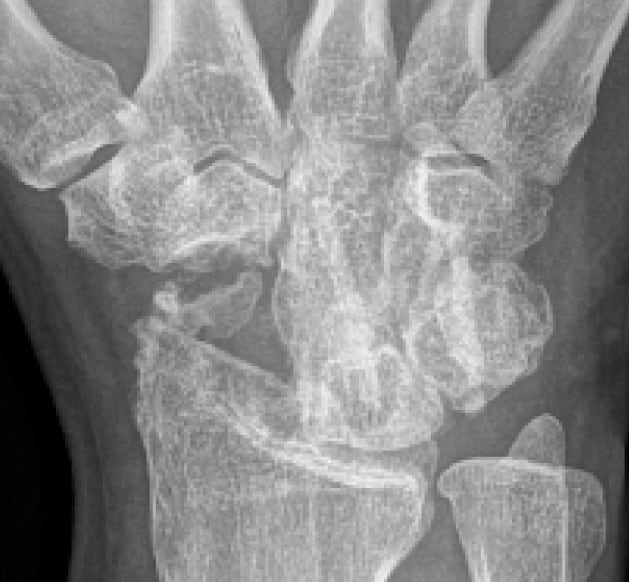

4 Monate postoperativ

Guter knöcherner Durchbau. Knochenschrauben-Transplantate beginnen mit Empfängerknochen zu verschmelzen.